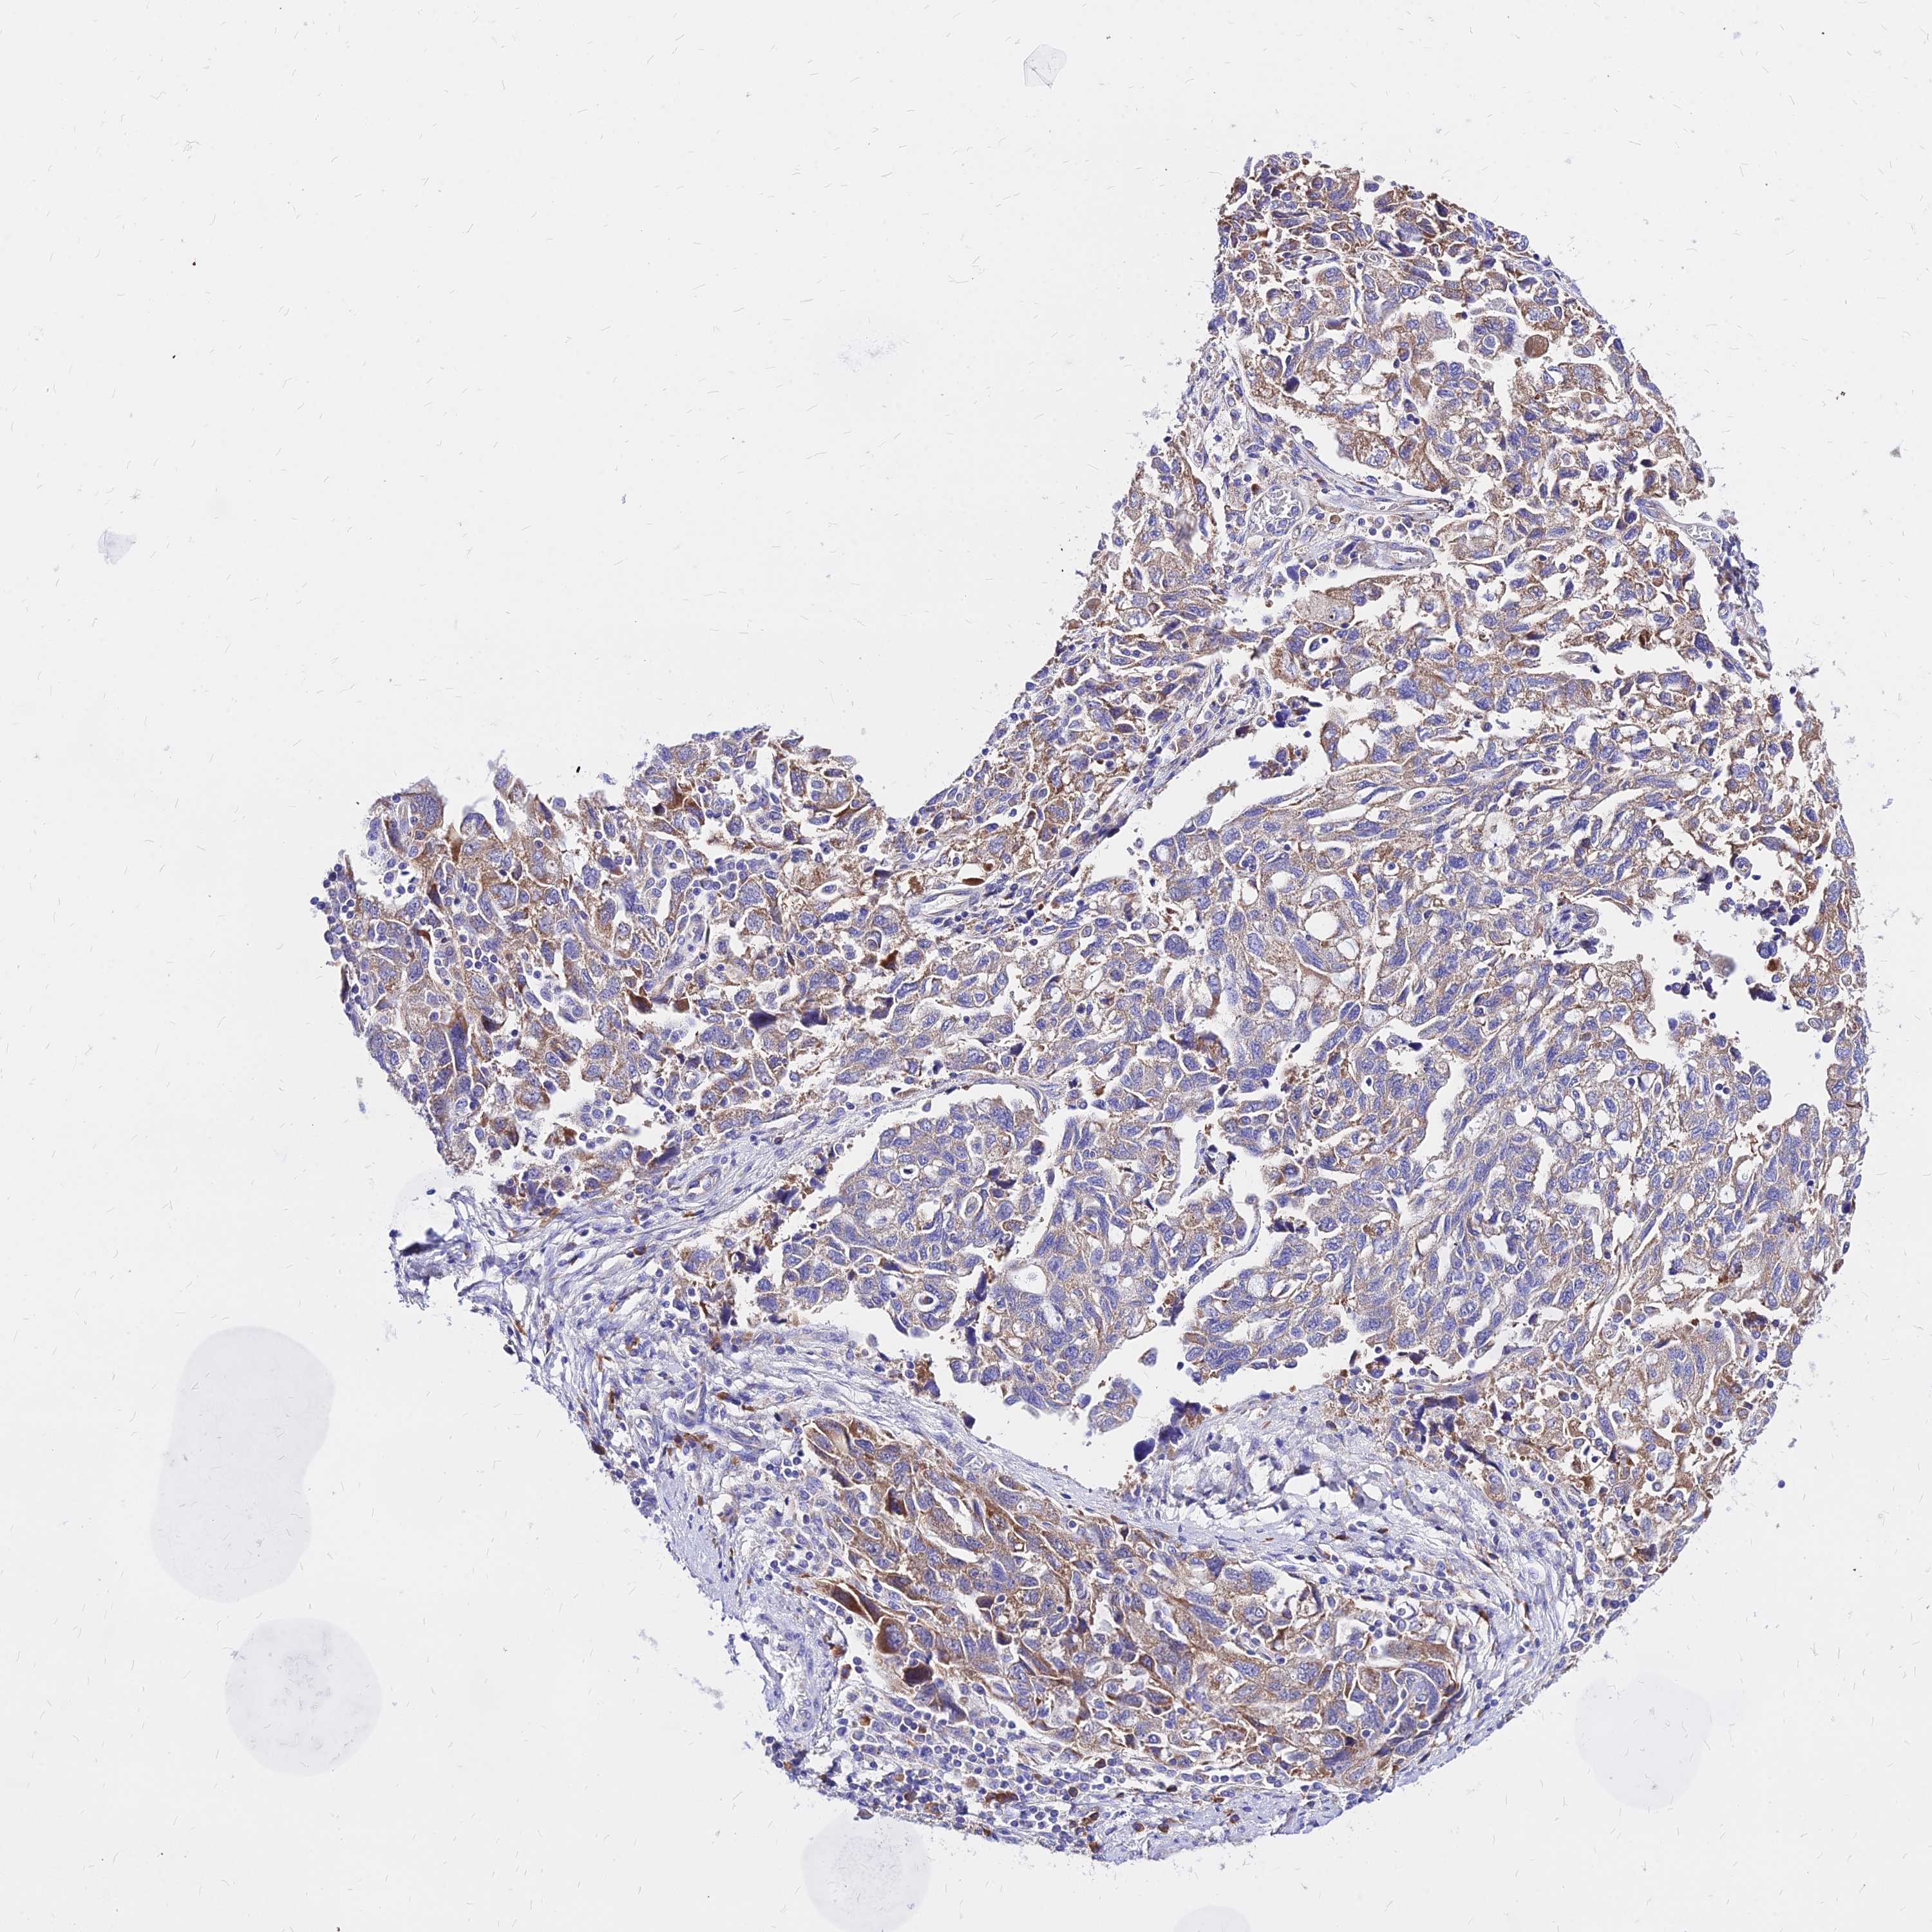

OVARIAN CANCER - Protein expressioni

A mouse-over function shows sample information and annotation data. Click on an image to view it in a full screen mode. Samples can be filtered based on level of antibody staining by selecting one or several of the following categories: high, medium, low and not detected. The assay and annotation is described here.

Note that samples used for immunohistochemistry by the Human Protein Atlas do not correspond to samples in the TCGA dataset.

Antibody stainingi

Antibody staining in the annotated cell types in the current human tissue is reported as not detected, low, medium, or high, based on conventional immunohistochemistry profiling in selected tissues. This score is based on the combination of the staining intensity and fraction of stained cells.

Each image is clickable and will lead to virtual microscopy that enables deeper exploration of all samples and also displays staining intensity scores, fraction scores and subcellular localization as well as patient and tissue information for each sample.

Antibody HPA043014

Staining

High

Medium

Low

Not detected

Intensity

Strong

Moderate

Weak

Negative

Quantity

>75%

75%-25%

<25%

None

Location

Nuclear

Cytoplasmic/membranous

Cytoplasmic/membranous,nuclear

Cystadenocarcinoma, serous, NOS

Carcinoma, NOS

Cystadenocarcinoma, mucinous, NOS

Carcinoma, endometroid